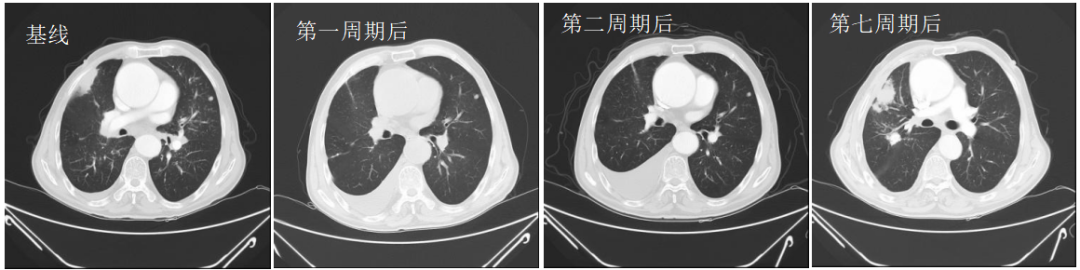

2022-08-15(治疗2周期后)CT、2022-09-28(治疗4周期后)CT、2022-11-08(治疗6周期后)CT:右肺上叶前段软组织密度影逐渐缩小(49mm*27mm→45mm*23mm→44mm*22mm),疗效综合评估SD。